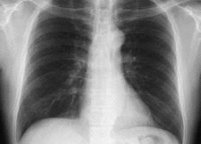

胸部単純X線

デジタル検診車

一般に、「レントゲン」と呼ばれる検査です。胸やお腹の写真、全身の骨の写真を撮ります。当院では、全てデジタルになっており、少ない放射線で高画質な画像を提供できます。画像は全てサーバーに転送され院内の電子カルテにて参照できるようになっています。